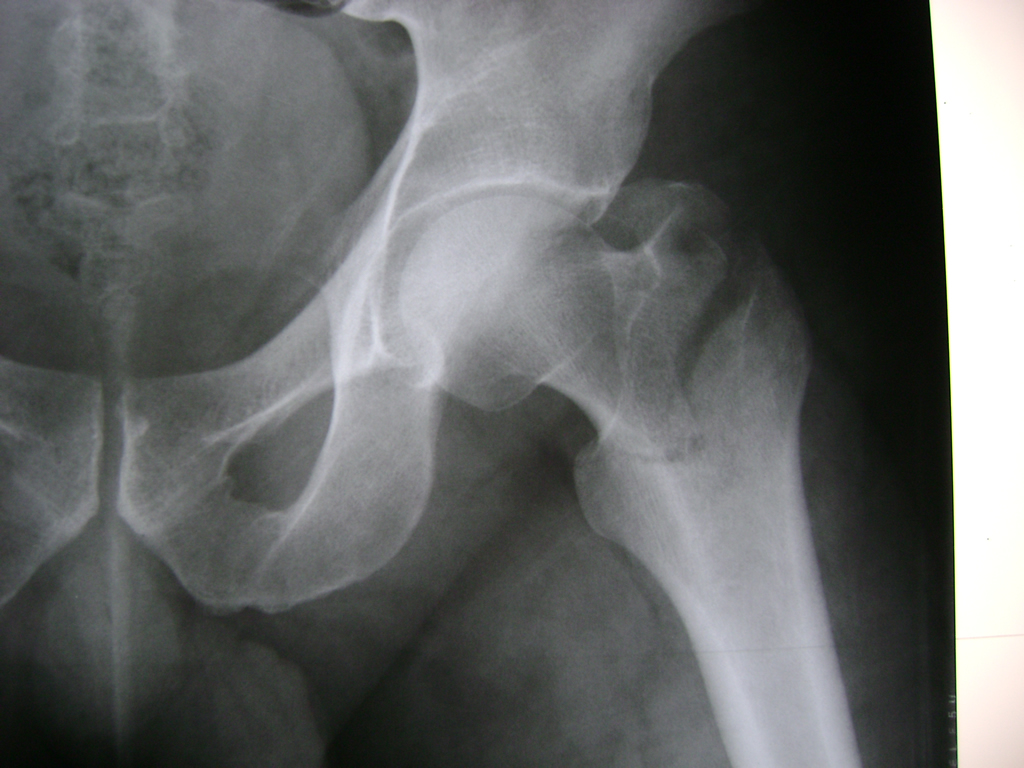

Cirugía de Cadera

La cirugía de fractura de cadera se realiza para reparar una ruptura en la parte superior del hueso del muslo. Este hueso se denomina fémur.

Es parte de la articulación coxofemoral. Si una fractura de cadera no recibe tratamiento, es posible que deba permanecer en una silla o en la cama.